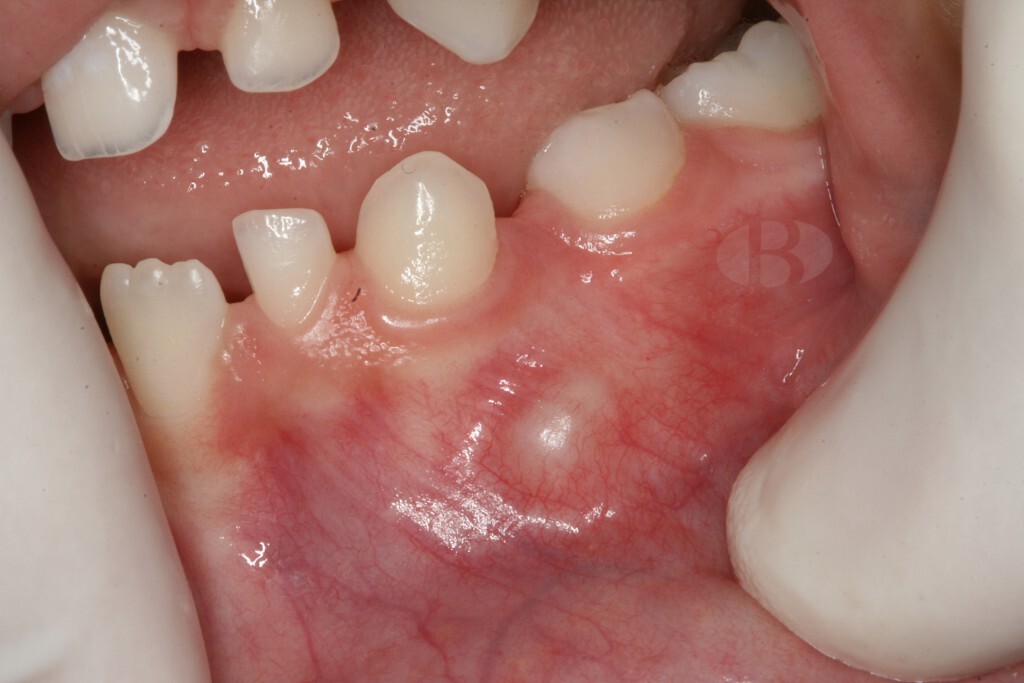

Phase 1: Gingivitis

Periodontitis and its precursor, gingivitis often go unnoticed until significant damage has already been done and in many cases – irreversible. Gingivitis is essentially inflammation of the gums, which in its turn is an effect of plaque buildup from inadequate oral hygiene. The bacteria in plaque produce toxins that can damage the gums and cause them to pull away from the teeth, forming pockets where more bacteria can accumulate. This vicious cycle leads to deepening of the pockets, and the gums starting to recede, exposing the roots of the teeth. This can cause sensitivity, pain, and eventually, tooth loss.

Risks of leaving gingivitis untreated

Gum disease often goes undetected and, when untreated, can cause irreversible damage to soft tissue and bone. This leads to gum recession, jawbone deterioration and eventually to tooth loss.

Progression to periodontitis

Periodontitis is a complex and mystifying process where certain types of bacteria cause damage to the gum tissue and bone structure supporting our teeth. As discussed it is usually preceded by gingivitis – the mild form of gum disease, that can progress to a more severe and damaging form.

Periodontitis begins with the accumulation of dental plaque, a biofilm composed of bacteria and extracellular matrix, on the teeth and gums. The bacteria in the plaque trigger the host’s immune response, leading to inflammation of the gingival tissue. The initial inflammatory response is characterized by increased blood flow and vascular permeability, which allows immune cells and proteins to infiltrate the affected tissue. In some individuals, the inflammatory response is not effectively resolved, resulting in persistent inflammation and destruction of the connective tissue and alveolar bone that support the teeth.

Early signs are often subtle, including bleeding gums, persistent bad breath, and slight discomfort while chewing. Without treatment, these symptoms worsen and more complications add up. Thus in the later stages of the disease, a person experiences bleeding and receding gums, deep pockets between the teeth and gums, loose teeth, changes in bite or tooth alignment, pus around the teeth and gums.